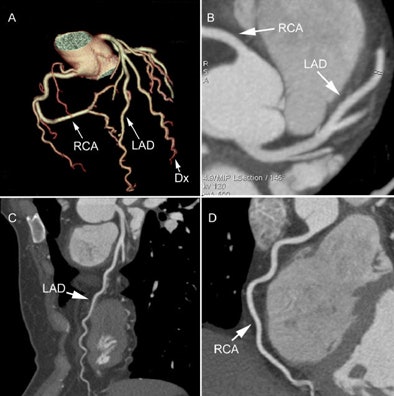

| A 40-year-old with risk factors for CAD and chest pain, worrisome for angina. Image demonstrates (A) 3D rendering of a right-dominant heart with (B) axial views of the left main artery, proximal left anterior descending (LAD) artery, and proximal right coronary artery (RCA) showing no plaque. Multiplanar reformatted views of the LAD (C) and RCA (D) also show no disease. Images courtesy of Dr. Jeffrey Schussler and Dr. Poorya Fazel. |